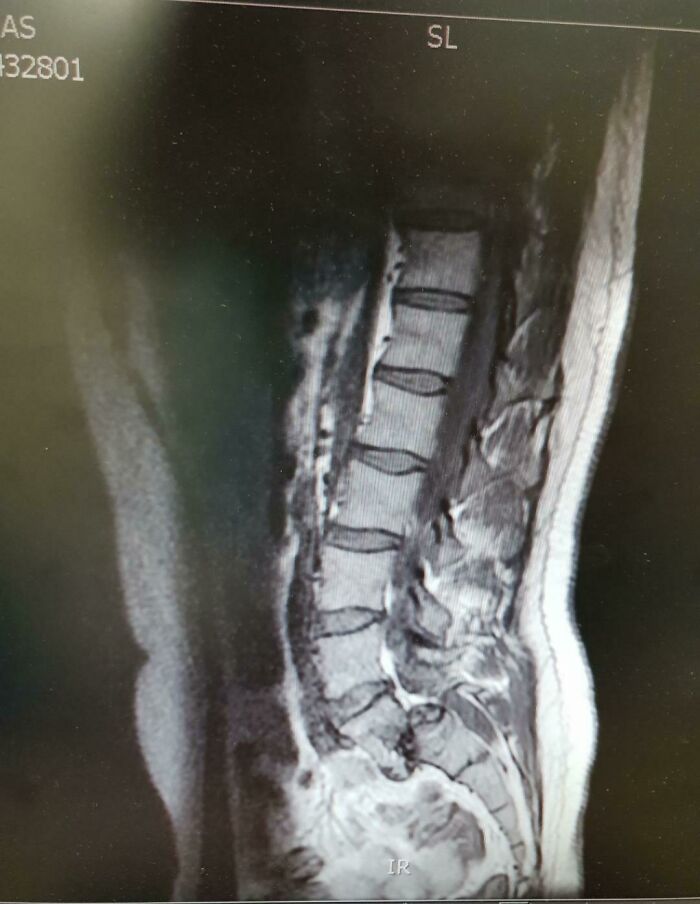

#70 I Was Diagnosed With Spondylolisthesis, A Condition Where A Vertebrae Moves Out Of Position. Managed To Run A 10k At 55mins While My Lower Back Looked Like This

Image source: GaryGump